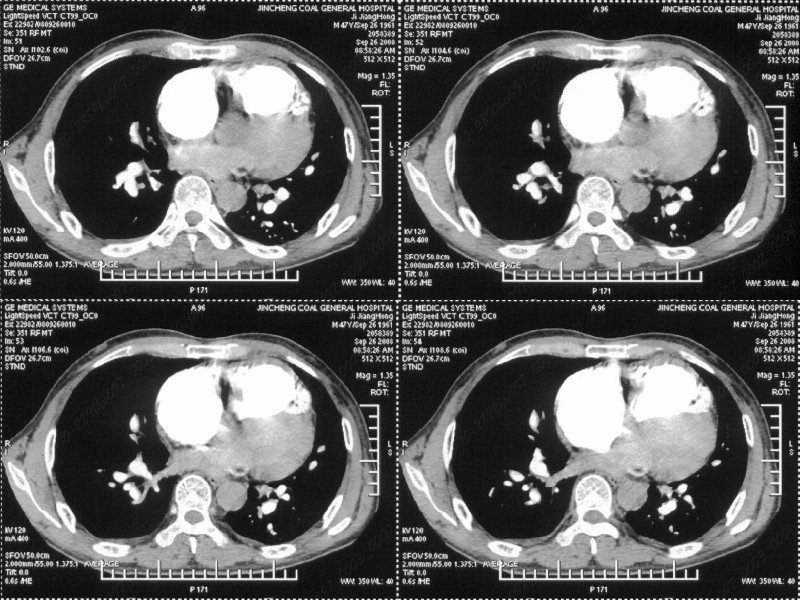

男性,47岁。胸部不适一年,ct检查发现右胸膜下结节。http://www.radida.com/bbs/forum.php?mod=viewthread&tid=46094

汇报临床诊断:右肺动脉分枝栓塞

考虑心脏疾患引起的右侧斜裂增厚。

右肺静脉充盈缺损,左心房体积小,右肺动脉远端动脉充盈缺损,右肺血管影细小,考虑;右肺动脉远端栓塞.

右肺中叶外侧段占位,考虑周围型肺癌伴局限性肺气肿,不除外炎性假瘤